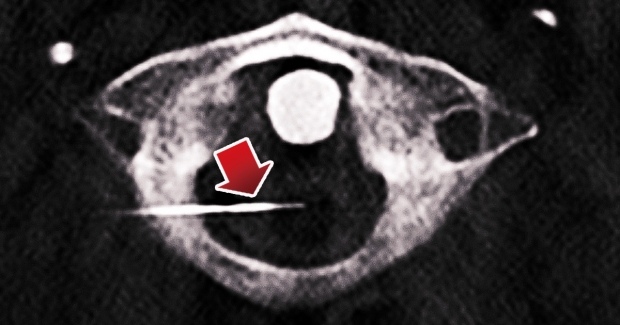

此手術屬微創性質,在麻醉科醫生密切監護下,患者於手術期間保持適度清醒。團隊利用術中電腦掃描造影,實時評估精準度,同時監察患者的感覺及動作反應,以確認插針位置正確無誤,隨後利用射頻消融切斷痛覺傳導束,令患者的疼痛感瞬間大大減輕。

手術期間,麻醉科醫生為何先生進行輕量鎮靜麻醉,隨後神經外科醫生於何先生的頸部插入刺針至脊髓。在進行感覺與行動測試、微調刺針位置後,便切斷相關痛覺傳導神經束。